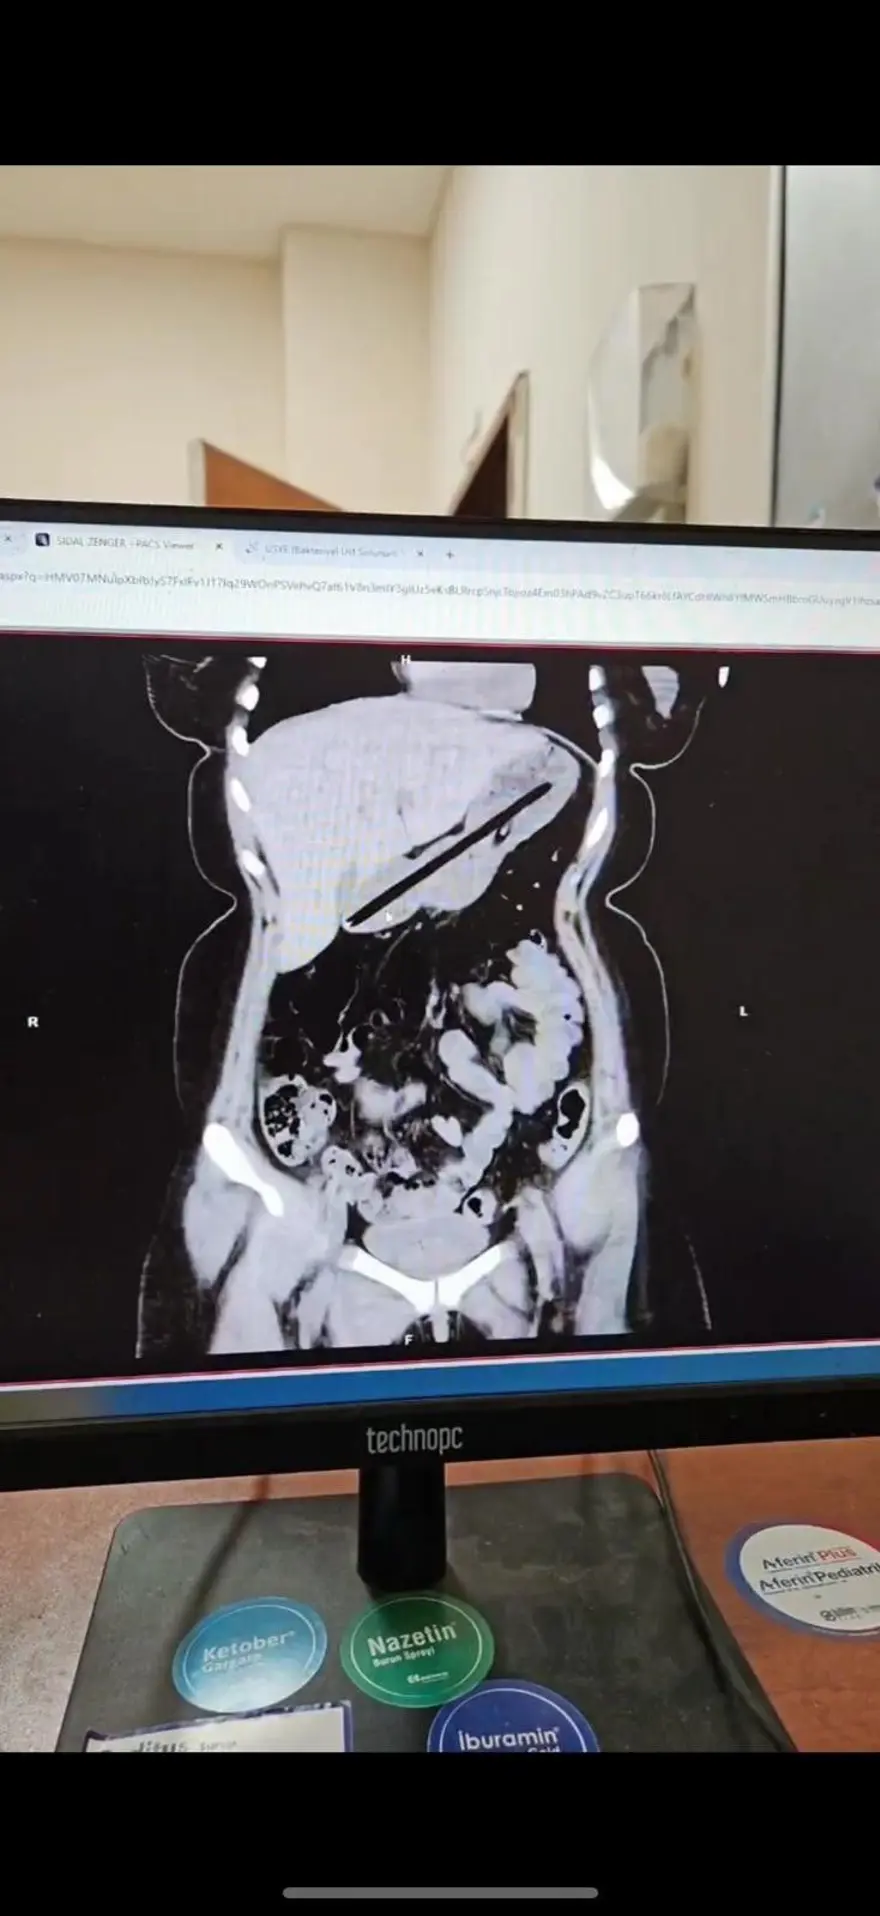

Hastanın midesinde yabancı cisim tespit edildi. Genel Cerrahi ekibince ertesi gün gerçekleştirilen yaklaşık bir buçuk saat süren endoskopi operasyonuyla genç kadının midesinden biri kurşun, diğeri tükenmez olmak üzere iki kalem çıkarıldı. Başarıyla sonuçlanan operasyonun ardından hasta bir gün müşahede altında tutularak taburcu edildi.

Operasyonu gerçekleştiren Dr. Öğretim Üyesi Adem Aslan, ilk kez böyle bir vakayla karşılaştıklarını belirterek, "22 yaşındaki bayan hastamız kalem yutma şikayetiyle ilçe devlet hastanemize başvurmuştu. Tomografisinde midesinde yabancı cisim olduğu görüldü. Biz de tetkiklerimizde midesinde kalem olduğunu gözlemledik.

Daha önce toplu iğne, kemik parçası gibi yabancı cisimlerle karşılaşıyorduk ama bu kadar uzun ve ince bir cisim ilk kez karşımıza çıktı. Midenin boşalması için bir gün bekledik ve ertesi gün yaptığımız endoskopide hastanın bir değil iki kalem yuttuğunu gördük.